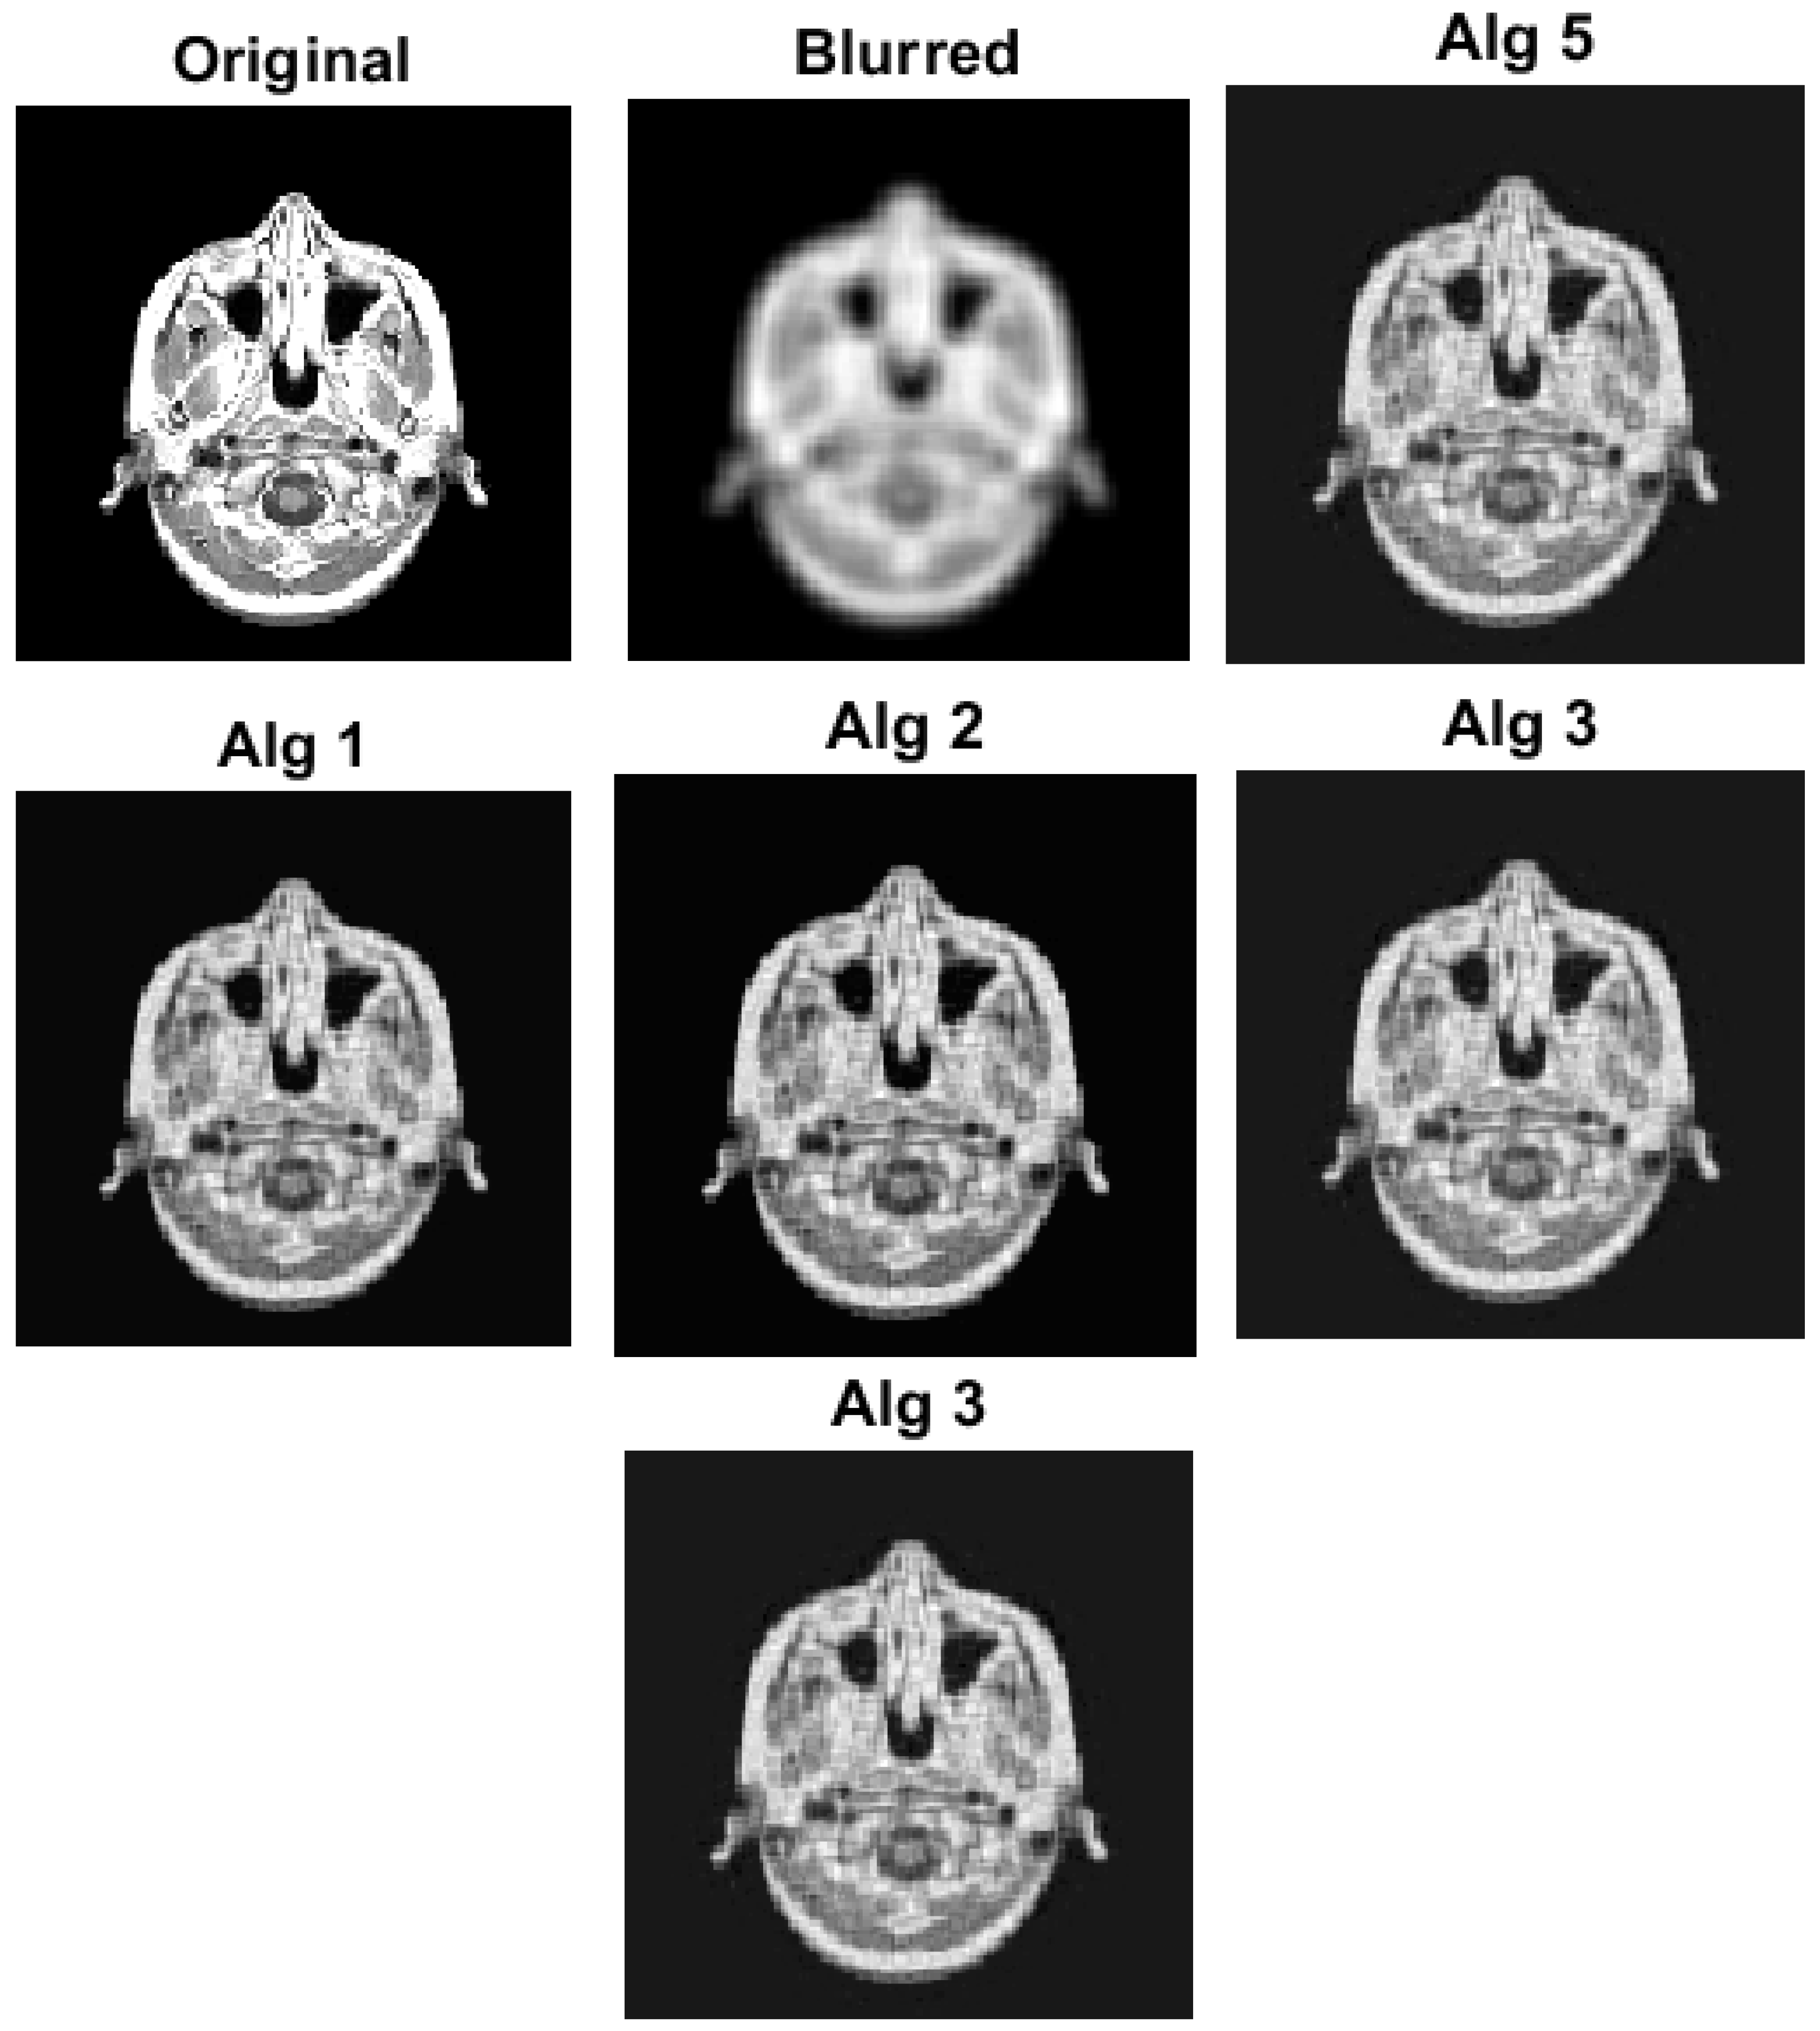

with a and a * being the original and restored images, respectively. In image restoration, the quality of the restored image is typically measured by its signal-to-noise ratio (SNR), where a higher SNR indicates better quality. To evaluate the effectiveness of our approach, we conducted experiments using three test images: Cameraman (256 × 256), Medical Resonance Imaging (MRI) (128 × 128), and Pout (400 × 318), all of which were obtained from the Image Processing Toolbox in MATLAB. Specifically, we degraded each test image using a Gaussian 7 × 7 blur kernel with a standard deviation of 4. We processed the algorithms using the following control parameters: Algorithm 11: θ n = 1 n 2 , η n = 2 n 1 8 n + 7 , β n = 1 r + 1 , λ n = 1 100 n + 1 , ξ = 1 , α = 0.4 g ( a ) = a 8 D ( a ) = 2 a . For Algorithm 1, we take θ n = n 7 n + 3 , λ = 0.05 ; for Algorithm 2, we take θ n = 1 n 2 , δ = 0.06 , λ = 0.09 ; for Algorithm 3, we take η n = 0.05 ; and for Algorithm 10, we take θ n = n 7 n + 3 , α n = 1 100 n + 1 , σ n = 1 2 B * B 2 . We also choose the initial values as a 0 = 0 R M × N and a 1 = 1 R M × N . The numerical results are shown in Figure 3, Figure 4, Figure 5 and Figure 6 and Table 2. It is easy to see that all the algorithms efficiently reconstruct the blurred image. Though the performance of the algorithms varies in terms of the quality of the reconstructed image, we note that Algorithm 11 was able to reconstruct the images faster than other algorithms used in the experiments. This also emphasizes the importance of the proposed algorithm.

Figure 4. Image reconstruction using MRI (128 × 128) image.

Mathematics 11 04708 g004